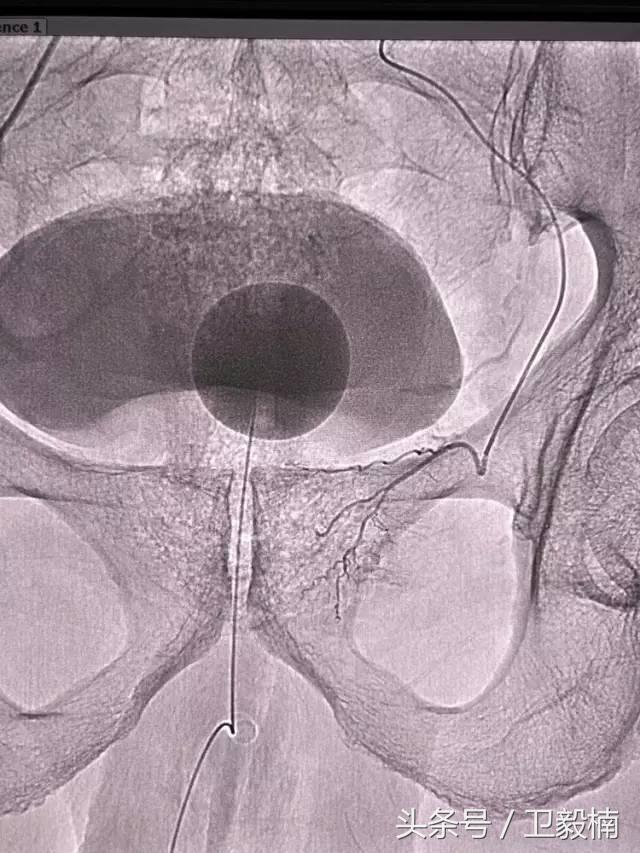

2、经导管血管栓塞法(Transcatheter embolization)

经原血管造影的导管或特制的导管,将栓塞物送至靶血管内,一是治疗内出血如外伤性脏器出血、溃疡病、肿瘤或原因未明的脏器出血。另一是用栓塞法治疗肿瘤,因肿瘤循环部分或全部被栓塞物阻断,以达控制肿瘤之生长,或作为手术切除的一种治疗手段;亦可用于非手术脏器切除,例如注射栓塞物质于脾动脉分支内,即部分性脾栓塞,以治疗脾功亢进,同时不影响脾脏的免疫功能。

常用的栓塞物质如自体血凝块、明胶海绵、无水酒精、聚乙烯醇、液体硅酮、不锈钢圈、金属或塑料小球及中药白芨等。